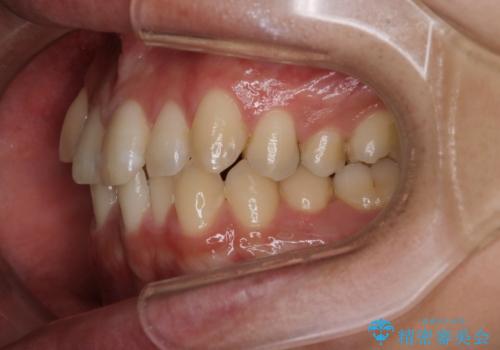

- 上の八重歯と下の歯のがたつきを主訴に来院されました。

矯正検査の結果、抜歯はせずに

臼歯を遠心移動させ、歯列をワイヤーで整えることでスペースを確保し、IPR(歯と歯の間を削る処置)を加えて歯並びを綺麗にする治療計画を立てました。

気にされていた八重歯とがたつきが綺麗に改善されました。